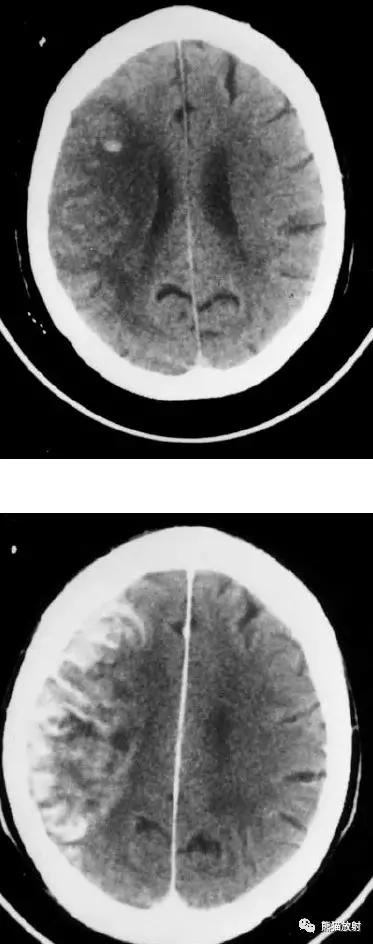

分水岭脑梗死(“Watershed” infarcts):右侧大脑前中动脉及中后动脉供血区之间梗死灶。

分水岭脑梗死:左侧深部和浅部大脑中动脉供血区之间梗死灶。